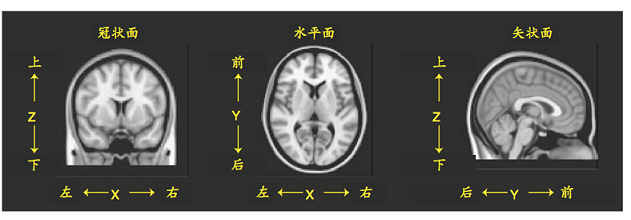

空间及坐标系

标准空间中,X代表左/右;Y代表前/后;Z代表上/下。在数据矩阵中,一个特定的体素可以被标记为[Xvox, Yvox, Zvox],通过这三个维度的坐标就可以确定体素的位置。